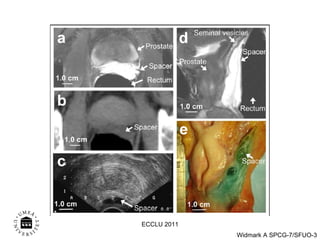

Prada et al Brachytherapy , 2007, 2009 ECCLU 2011

Principal of the No-HARM study Needel operated Hyaluronic Acid for Rectal Move HA 10% 50% 70% 10% 70% 50% ECCLU 2011

Prada et alBrachytherapy , 2007, 2009 ECCLU 2011

Principal of theNo-HARM study Needel operated Hyaluronic Acid for Rectal Move HA 10% 50% 70% 10% 70% 50% ECCLU 2011